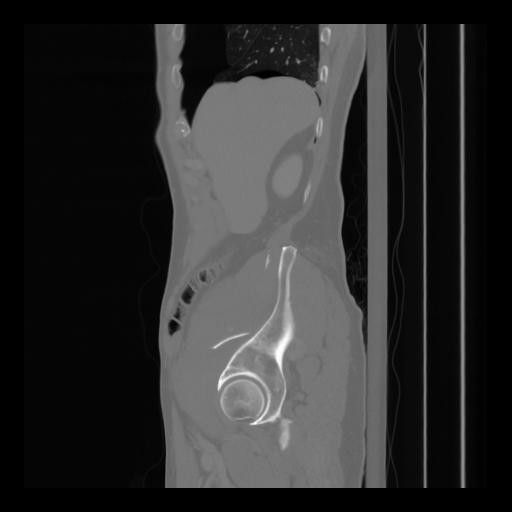

36 CUERPO,CE,Sagittal,3.000,CUERPO,Sagittal,